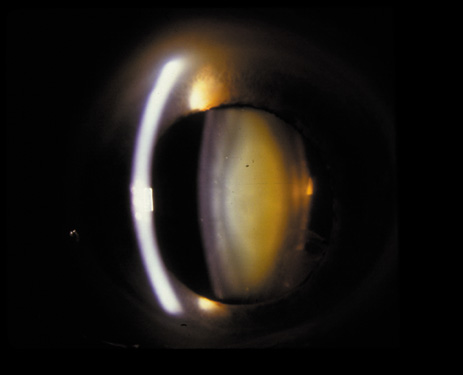

The PSC is the least prevalent subtype in most population-based studies.18 These cataracts often occur in combination with nuclear or cortical cataracts in the later stages. They are easily noticed on retroillumination because they are usually located centrally, and may interfere with funduscopy (Fig. 12). In early stages, patients usually complain of subjective symptoms such as glare disability32 and difficulty focusing on near objects. This is because when the pupil constricts during accommodation, the light entering the eye becomes concentrated centrally, where the PSC is also located. This causes light scattering and interferes with the ability of the eye to focus an image on the macula. In addition, these opacities lie at or near the nodal point of the eye, further interfering with focusing of the image on the macula.

Fig. 12. PSC. Note the central location, which gives rise to severe glare disability.

One can examine this type of cataract with direct illumination, using the narrow and broad beams of the slit-lamp to show the characteristic granular inner surface immediately in front of the posterior capsule (Fig. 13). The problem with this technique, however, is that patients may not tolerate any prolonged direct illumination because of the glare. Retroillumination is therefore more useful for revealing the outline of the opacity, since it is usually seen as an “island” in the center of the posterior capsule, which is further highlighted by the shadow cast by the opacities.33 However, in the early stages of this type of cataract, the dust-like particles that might be noticeable in the central posterior subcapsular area with direct illumination disappear or are difficult to see with retroillumination (Fig. 14). Eventually this “dusting” becomes dense enough to cast a shadow and thus appear on retroillumination. The smooth orange background of the fundus helps to highlight the rough, irregular pseudopodia-like edges of the central opacity. In advanced stages, the PSC may become a thick, calcified plaque (Fig. 15). During surgery, excessively vigorous scraping or vacuuming of the calcified opacity can lead to rupture of the posterior capsule. Usually, small remnants that are left behind after surgery are reabsorbed and do not interfere with vision; otherwise, they are easily treated with a neodymium : yttrium (Nd:YAG) aluminum garnet laser. Pathologic evidence suggests that most PSCs result from the migration of bow region cells into the potential space (along with accumulated cellular debris) between the posterior capsule and the cortex.34–36

Fig. 13. Direct slit-lamp illumination of a PSC, showing an irregular granular surface in front of the posterior capsule.